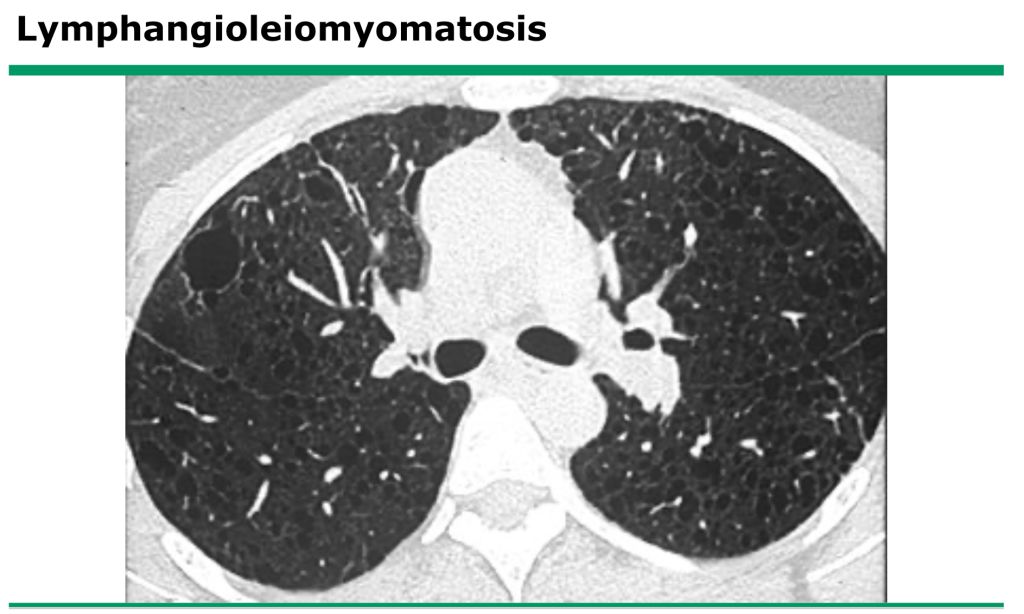

74.一位30歲女性至急診就醫,主訴突發性胸痛,長期呼吸困難,胸部電腦斷層影像如附圖,下列 敘述何者錯誤?

(A)影像表現與 tuberous sclerosis在肺部的病灶相似度高

(B)此病人可能發生自發性氣胸

(C)男性的發生率與女性相當

(D)除了肺部之外,也可能會在腎臟、神經系統等部位出現異常